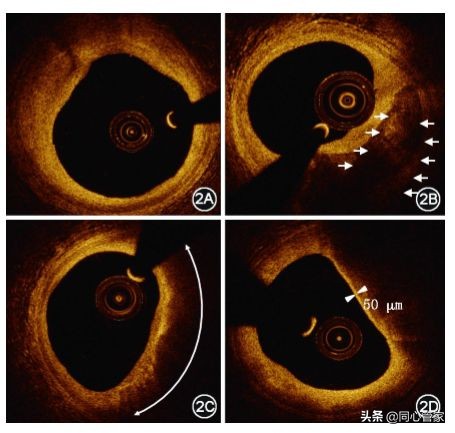

OCT“眼中”的斑块:

- 纤维斑块:强反射,均匀增生;中膜也能分得清 。

- 钙化斑块:里面密度不均一 ,外面边界很锐利。

- 脂质斑块:强衰减,信号低,边界变得不清晰(如图所示)

▲OCT检查图像斑块类型(2A:纤维斑块;2B:钙化斑块;2C:脂质斑块;2D:薄纤维帽粥样硬化斑块) [3]。